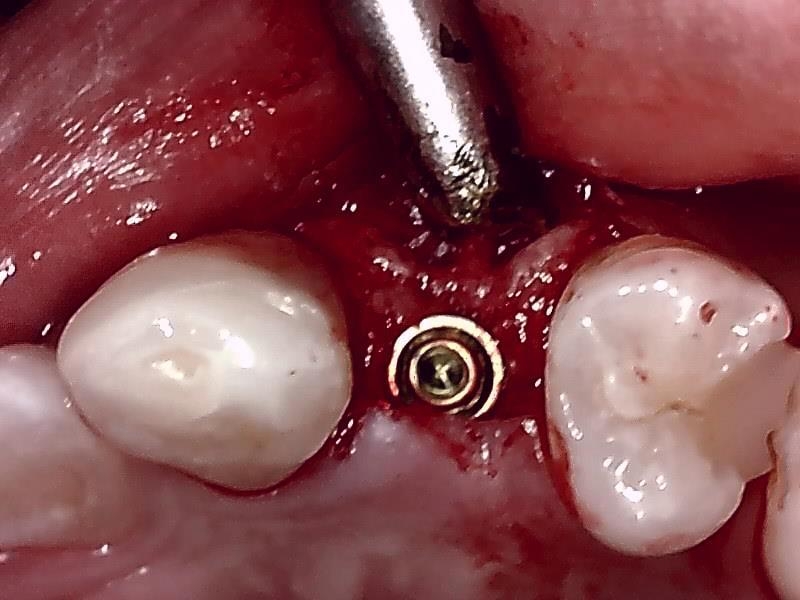

切開して歯肉剥離

ドリリング

インプラント体の埋入

ヒーリングアバットメント装着

骨造成 自家骨移植

縫合